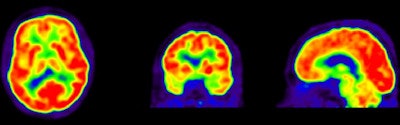

FDG-PET images show a normal brain (top) with normal functions (red) compared with an abnormal brain (bottom) with a diagnosis of Alzheimer's and lack of FDG uptake (yellow and green).In addition, two-year clinical follow-up in a subsample of 39 patients showed that PiB and FDG predicted progression to Alzheimer's disease for patients with mild cognitive impairment, and that the diagnosis of dementia established after PET remained unchanged in 96% of the patients.